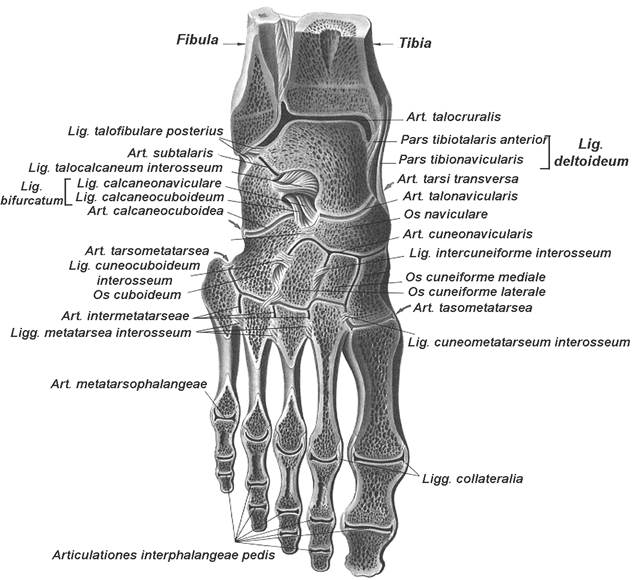

Анатомия суставов Шапарова и Лисфранка: фото и информация